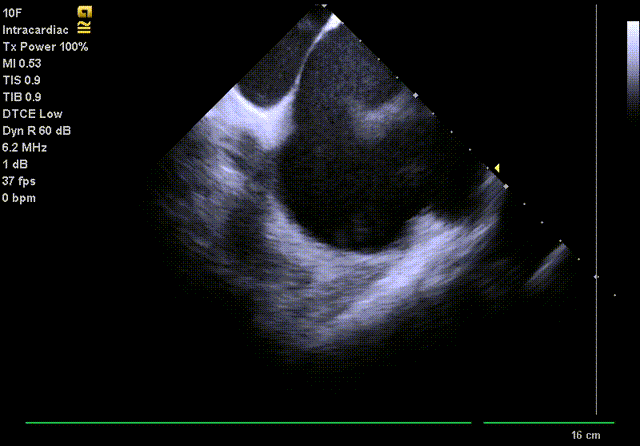

通过ICE再次确认LAA无血栓,并指导房间隔穿刺位置;

通过ICE进行LAA血栓筛查